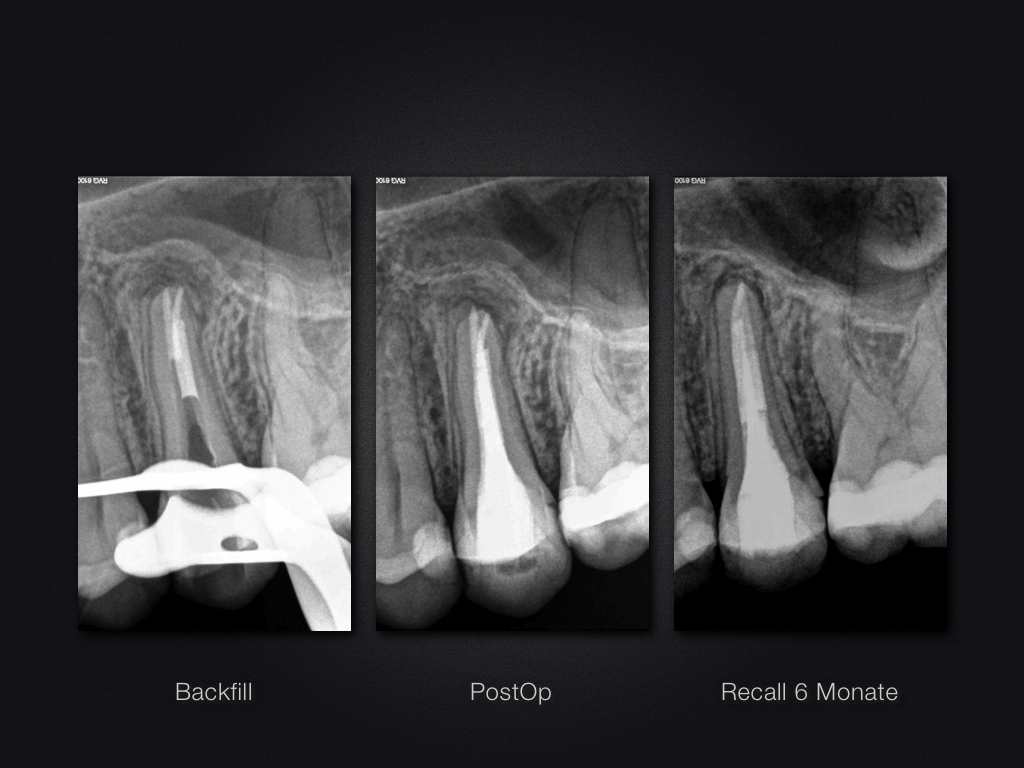

25D.004

Auftrag erfüllt …